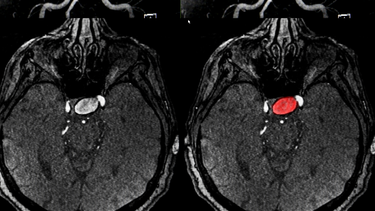

Xuất huyết não xảy ra khi mạch máu não bị vỡ, khiến máu thấm vào mô não và làm tổn thương các tế bào thần kinh, bệnh nhân sau xuất huyết não để lại ít nhất một dạng di chứng thần kinh. Mức độ nặng nhẹ phụ thuộc vào vị trí tổn thương, lượng máu chảy và thời điểm cấp cứu. Dưới đây là những di chứng phổ biến nhất mà người bệnh cần lưu ý: